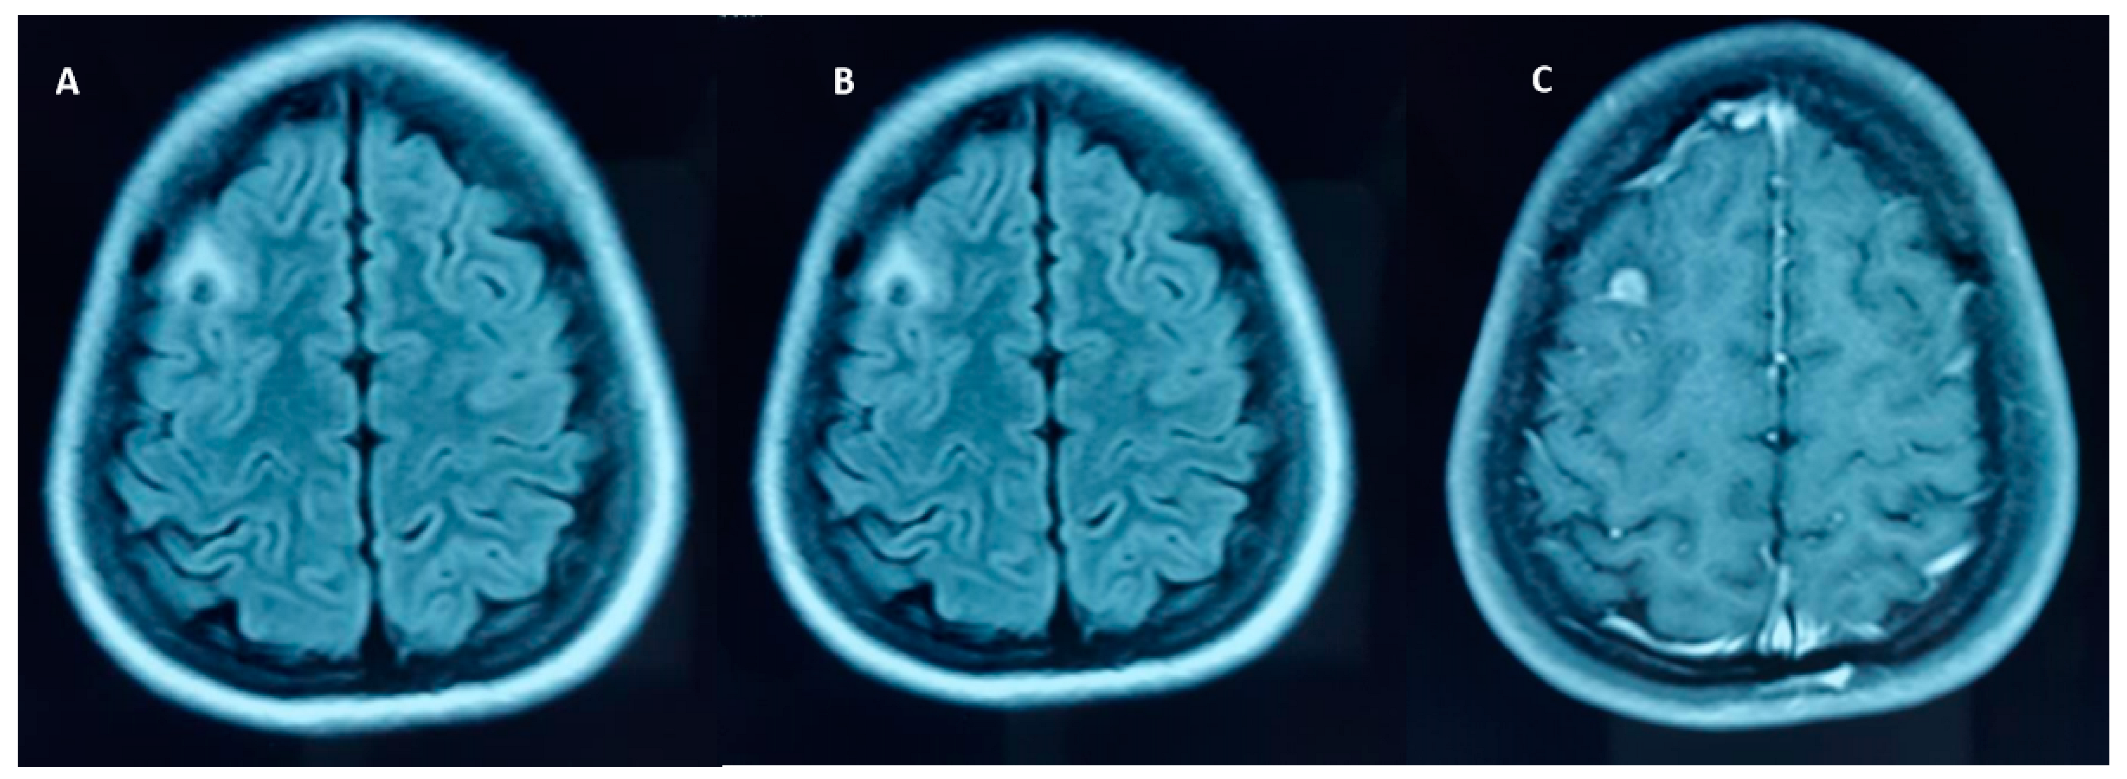

5. Calcified NCC: Epileptogenesis

- Jama-António, J.M.C.; Yasuda, C.L.; Cendes, F. Intermittent perilesional edema and contrast enhancement in epilepsy with calcified neurocysticercosis may help to identify the seizure focus. Epilepsia Open 2019, 4, 351–354. [Google Scholar] [CrossRef]

- Nash, T.E.; Pretell, E.J.; Lescano, A.G.; Bustos, J.A.; Gilman, R.H.; Gonzalez, A.E.; Garcia, H.H. Cysticercosis Working Group in Peru, Perilesional brain edema and seizure activity in patients with calcified neurocysticercosis. Lancet Neurol. 2008, 7, 1099–1105. [Google Scholar] [CrossRef] [PubMed]

- Nash, T. Edema surrounding calcified intracranial cysticercosis: Clinical manifestations, natural history and treatment. Pathog. Glob. Health 2012, 106, 275–279. [Google Scholar] [CrossRef] [PubMed]

- Fujita, M.; Mahanty, S.; Zoghbi, S.S.; Araneta, M.D.F.; Hong, J.; Pike, V.W.; Innis, R.B.; Nash, T.E. PET Reveals Inflammation around Calcified Taenia solium Granulomas with Perilesional Edema. PLoS ONE 2013, 8, e74052. [Google Scholar] [CrossRef]

- Gupta, R.K.; Kumar, R.; Chawla, S.; Pradhan, S. Demonstration of Scolex within Calcified Cysticercus Cyst: Its Possible Role in the Pathogenesis of Perilesional Edema. Epilepsia 2002, 43, 1502–1508. [Google Scholar] [CrossRef]